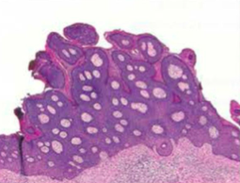

Condyloma

Warty neoplasm on vulva Causes: - HPV 6/11 --> condyloma acuminatum (koilocytic change but low risk progression to carcinoma) - 2ndary syphillis --> condyloma latum